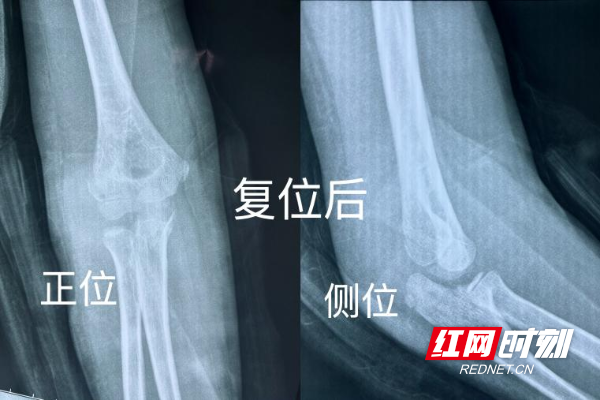

复位过程中,正骨中心技术顾问郭升辉主任医师凭借数十年临床积累的丰富经验,以及“手摸心会、稳准轻快”的精湛中医正骨技艺,精准把控复位角度与力度,仅通过纯手法操作,便成功为患儿实现骨折近解剖复位。复位后检查结果显示,骨折对位对线完全达到临床满意标准。为助力患儿快速康复,还同步制定了个性化早期功能锻炼指导,全程跟踪恢复情况。